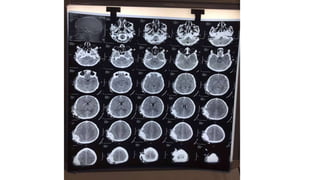

• On CT scan, an epidural hematoma is characterized by a biconvex, uniformly

hyperdense lesion

• Presence of low-density areas within EDH and/or evidence of contrast

extravasation into the hematoma on postcontrast head CT are indications of

hyperacute/active bleeding into the hematoma

Radiographic progression

• Type I (acute or hyperacute): day 1, associated with a “swirl” of unclotted blood)

• Type II (subacute): days 2 to 7, solid

• Type III (chronic): days 7 to 20, mixed or lucent with contrast enhancement

• Occur in 58%, 31%, and 11% of cases, respectively.

Zimmerman RA, Bilaniuk LT. Computed tomographic staging of traumatic epidural bleeding.